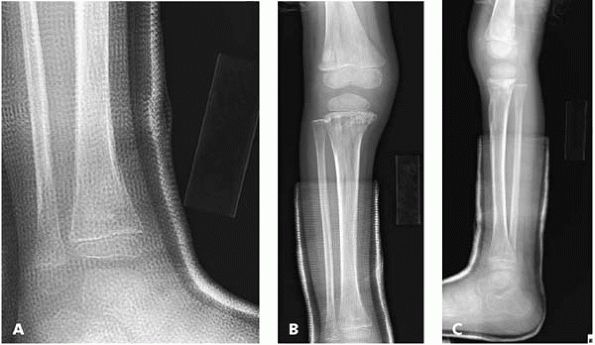

Likewise, leukemia, which presents as musculoskeletal pain 25% of the

time, may result in an increase, decrease, or no change in tech99 uptake4 (Fig. 11-4).

▪ FIGURE 11-4

Leukemia presenting as a limping child. This 3-year-old presented for a second opinion regarding persistent limping after an “ankle fracture” diagnosed at an outside hospital. A: An AP view of the ankle showed no clear sign of a fracture, but did show an irregular appearance to the bone. Fortunately, the treating pediatric orthopaedist sent the child back for a full-length AP and lateral of the tibia. AP (B) and lateral (C) of the entire tibia and distal femur show marked irregularities of the metaphyseal bone at the knee consistent with a systemic process. A rapid and aggressive workup quickly revealed that this child had leukemia. (Case courtesy of R. Davidson, MD.) |